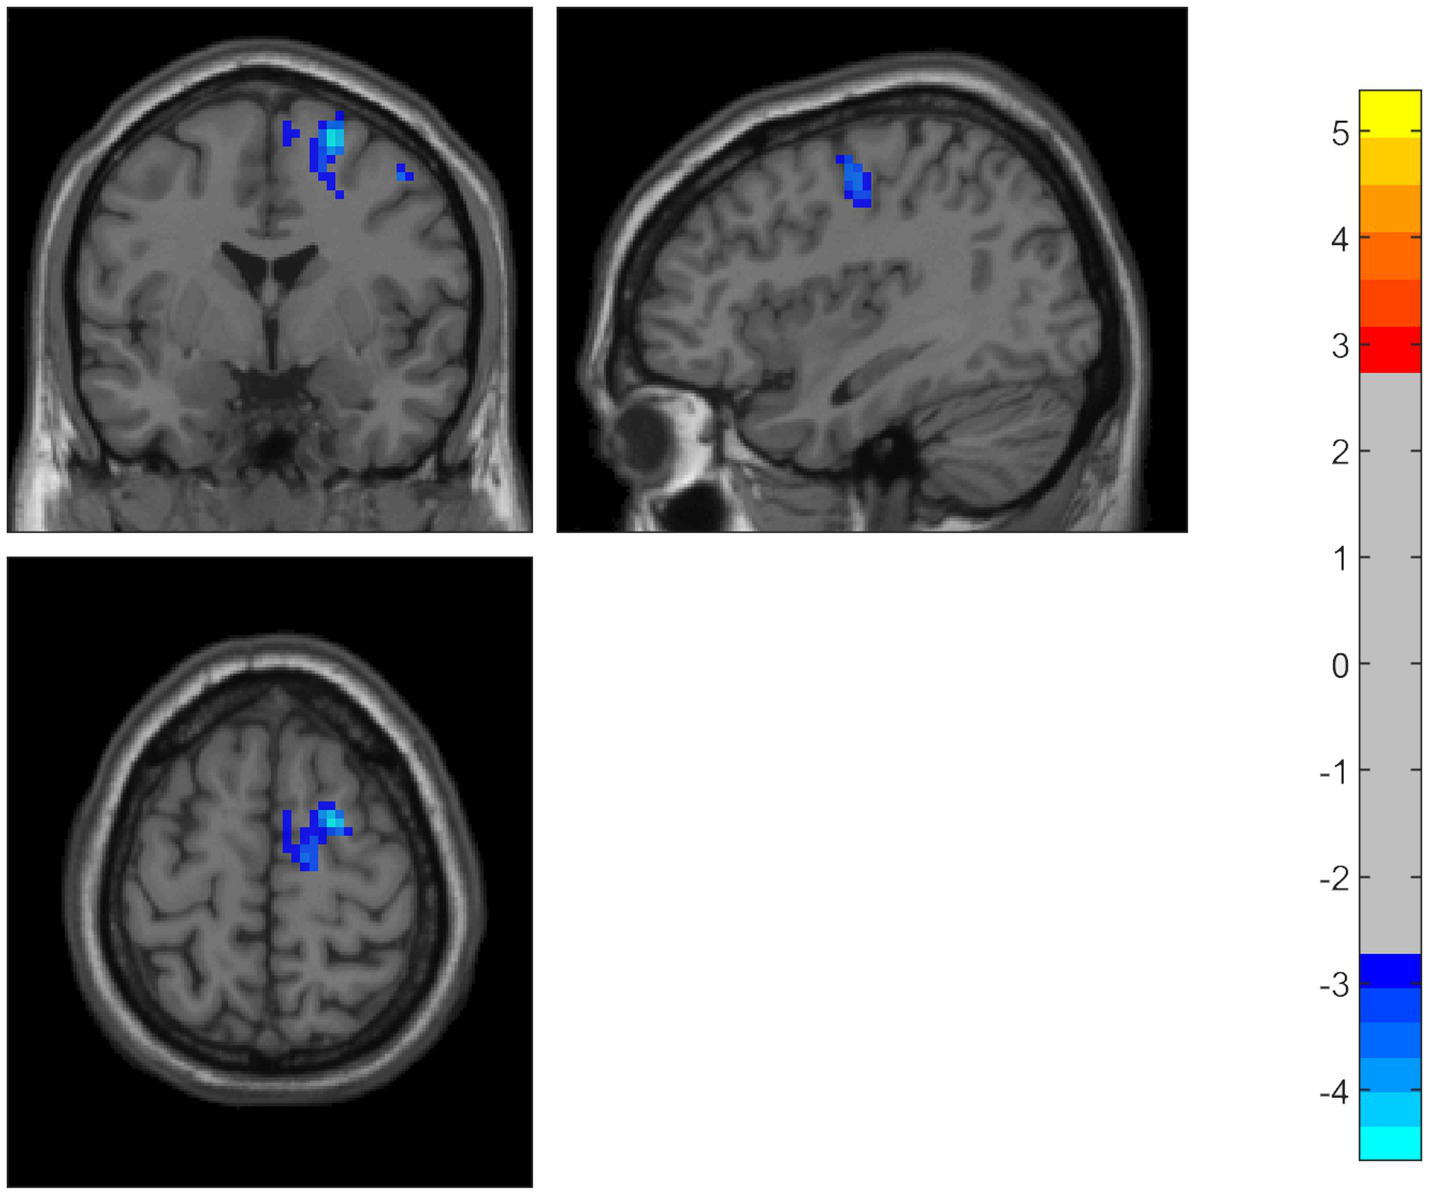

Compared to the HC group, the PD patients showed significantly decreased ALFF in the middle temporal gyrus, temporal pole, and superior temporal gyrus on the left side. Using the temporal pole as the ROI, PD patients also exhibited decreased connectivity between the temporal pole and the superior frontal gyrus (SFG), dorsolateral supplementary motor area (SMA), and precentral gyrus on the right side (GRF correction, p < 0.05) (Table 2 and Figures 1, 2).

Figure 2. Using the temporal pole as the ROI, PD patients also showed decreased connectivity between the temporal pole and the superior frontal gyrus, dorsolateral supplementary motor area, and precentral gyrus. The color bar represents T-values. Brighter colors represent higher values.